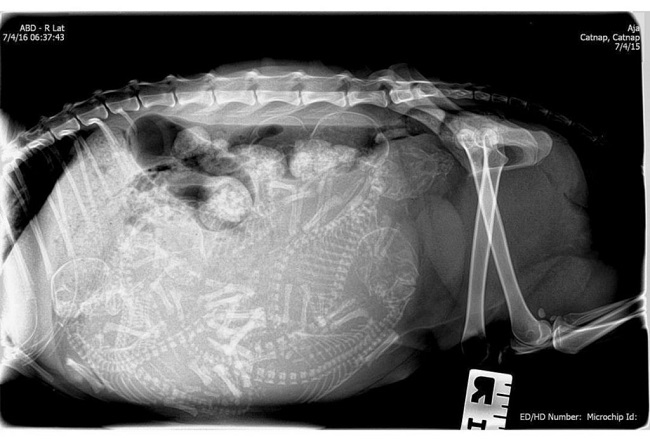

We bet you are mostly ignorant about your favourite domestic animal. But all kittens are born with blue eyeballs. They change colour a few months after their births and you can only tell their final colour at least three months after their births.

Image Source: onedio.com